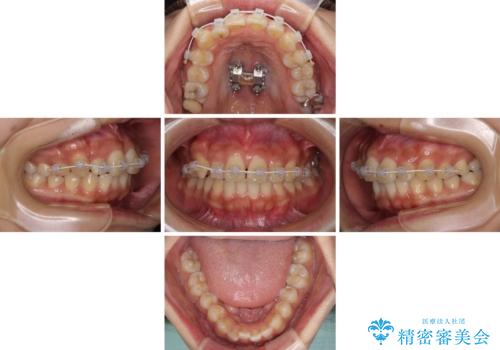

- 矯正装置

- インビザライン

- 治療期間

- 2年4ヶ月

上下の骨幅を改善したことで、スムーズに歯列矯正を行うことができました。